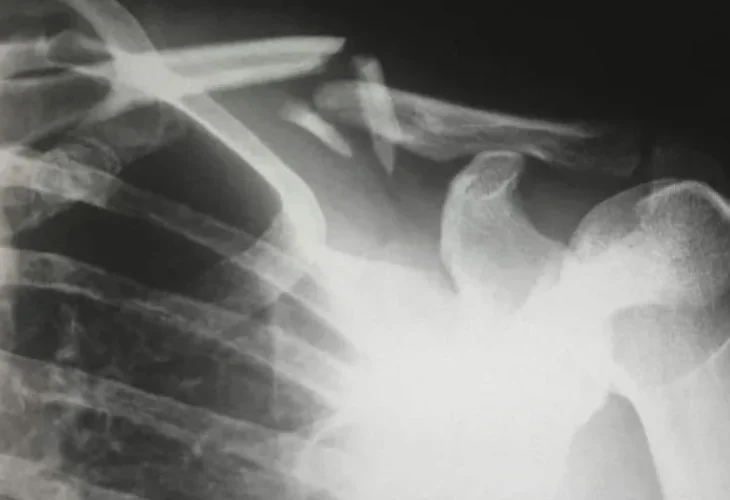

מקרה נדיר הגיע לאחרונה לרופאי בית החולים 'שין דו' בצ'נגדו שבסין: אישה עם מחסור חמור בוויטמין D, שנגרם משימוש מופרז בקרם הגנה, סבלה משבר בעצם רק מסיבוב 'אגבי' במיטתה.

בדיקות שבוצעו לאישה בבית החולים הראו שרמות הויטמין D בגופה נמוכות מהרגיל, מה שככל הנראה האיץ את אובדן העצם, וגרם להופעת אוסטאופורוזיס חמורה.